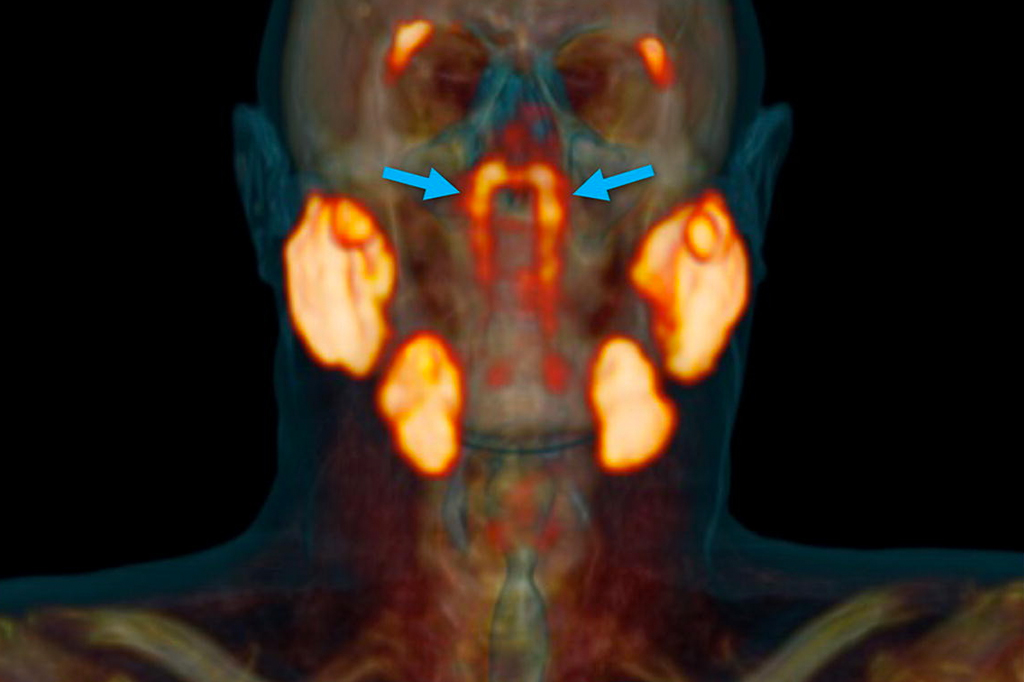

Pesquisadores podem ter encontrado duas novas glândulas no crânio humano

Por Carolina Fioratti 22 out 2020, 17h31 | Atualizado em 25 jul 2022, 10h39